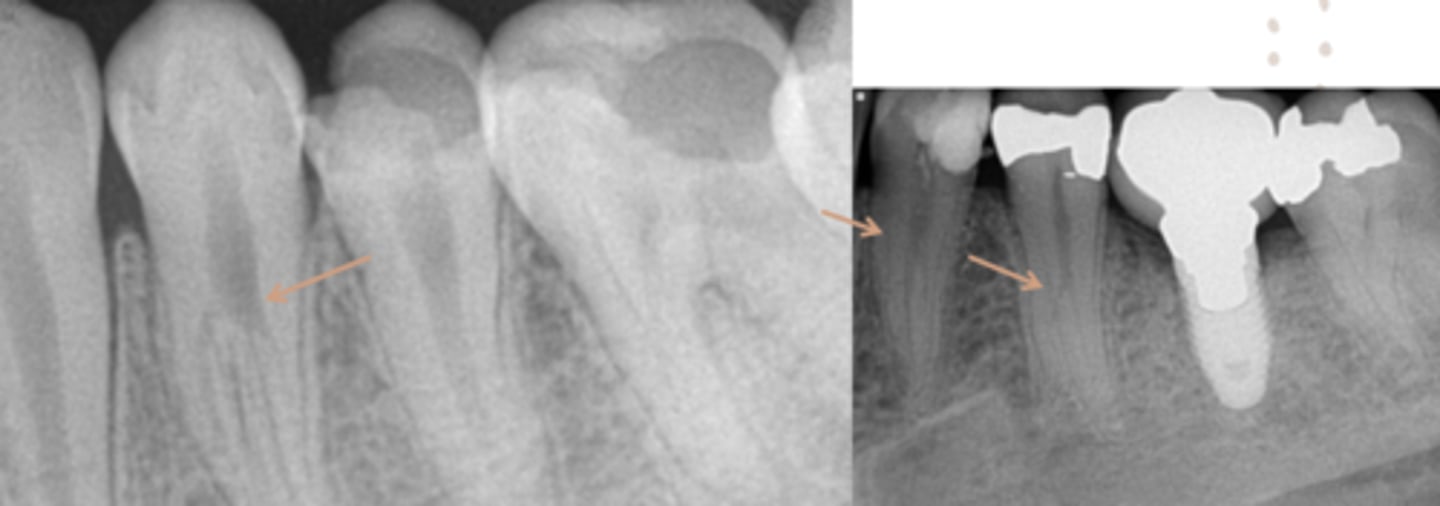

ID the problems:

Areas of rarefaction

ID the problem:

splitting canals

fracture

vertical root fracture

- May not show on PA radiographs

Presents with signs of:

- J-shaped lesion/lateral radiolucency

- Isolated deep pocket

- Coronally located swelling or sinus tract